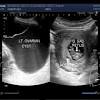

Back pain would seem reasonable too. Each year, according to the centers for disease control and prevention (cdc). Hi, this is my first time posting, i'm worried i might have ovarian cancer, i had pain in my pelvic area for 3 months now, at times it can be very painful and hurts when i walk, or move, i've also got a bloated tummy ( i've been asked several times if i'm pregnant it's that big) also suffering with indegestion, i'm not eating but have put on some weight, my periods are every 6 weeks and a. Ovarian cancer is one of the most misdiagnosed diseases because its symptoms are so similar to many benign conditions. How the simple urine test presents a positive or negative result;

The Signs Of Ovarian Cancer Are General So Here S What To Look For Hellogiggles from imagesvc.meredithcorp.io The symptoms that can be common to both ovarian cancer and pregnancy are as follows: It's important to know what the warning signs are, as well as when to seek medical attention. What happens in your body in early pregnancy to generate the identifiable hormone 'hcg'; If any occur, they tend to be very general. I heard that a pregnancy can be mistaken for a cyst ovarian cyst and pregnancy? Quickly feeling full when eating. There are different types of ovarian cancer that can develop depending on where exactly in the ovaries has cancer began. Back pain would seem reasonable too.

I have an app soon but i am freaking out it could be a mass or ovarian cancer. How the simple urine test presents a positive or negative result; No, the procedure does not lead to cancer. Cancer refers to a disease in which mutated cells grow abnormally and rapidly in the body and may spread from one organ or area to another. As the number of pregnancies increases, the risk of ovarian cancer decreases. To compound this difficulty, unlike breast cancer, where you may feel a lump, or cervical cancer, which can be picked up through a smear result, the key symptoms for ovarian cancer, particularly. Creation of the pregnancy indicator hcg in normal pregnancy Doctors in 147 specialties are here to answer your questions or offer you advice, prescriptions, and more. Pelvic discomfort, abdominal swelling and/or bloating, urinary frequency, constipation, abnormalities in menstruation, nausea, and vomiting, and fatigue. While ovarian cancer has the lowest survival rate for all cancers, 92 per cent of patients will. What happens in your body in early pregnancy to generate the identifiable hormone 'hcg'; Ovarian cancer may cause no symptoms in the early stages. It is highly recommended that surgery is carried out before pregnancy, so as to avoid complications.